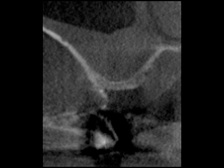

術前のCT画像、このように骨の厚みがほとんどありません

CTで人工骨がインプラントの周りに入っているのを確認しています。

サイナスリフトをする場合、CTがないと成功しているかの確認が難しいと思われます。